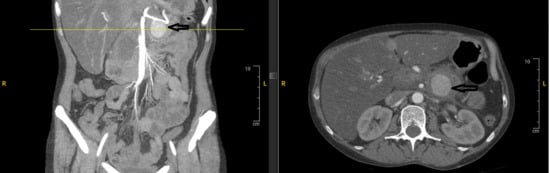

Background and Clinical Significance: Splenic artery pseudoaneurysm (SAP) is a rare but life-threatening complication of chronic pancreatitis. Although endovascular embolization achieves high technical success, recurrence and delayed rupture may occur, particularly in patients with ongoing pancreatic inflammation or alcohol use disorder (AUD). Case Presentation: A 47-year-old woman with alcohol-associated chronic pancreatitis presented with hematochezia, melena, and syncope. CT angiography revealed a 3.6 cm SAP adjacent to a 4.2 cm pancreatic head pseudocyst, and she underwent successful coil embolization. Despite initial stability, she relapsed into heavy alcohol use, experienced recurrent pancreatitis flares, and developed progressive multisystem comorbidities. Surveillance imaging up to three months post-embolization showed pseudocyst fluctuations without early recanalization, but long-term follow-up lapsed. Eight months after embolization, she presented in hemorrhagic shock from recurrent SAP rupture and died despite massive transfusion and emergent splenic artery ligation. Conclusions: Fatal SAP rupture may occur months after technically successful embolization. Sentinel bleeding, AUD relapse, and progressive systemic decline are critical warning signs. Structured post-embolization imaging and multidisciplinary management are essential to improve long-term outcomes. Full article

Figure 1